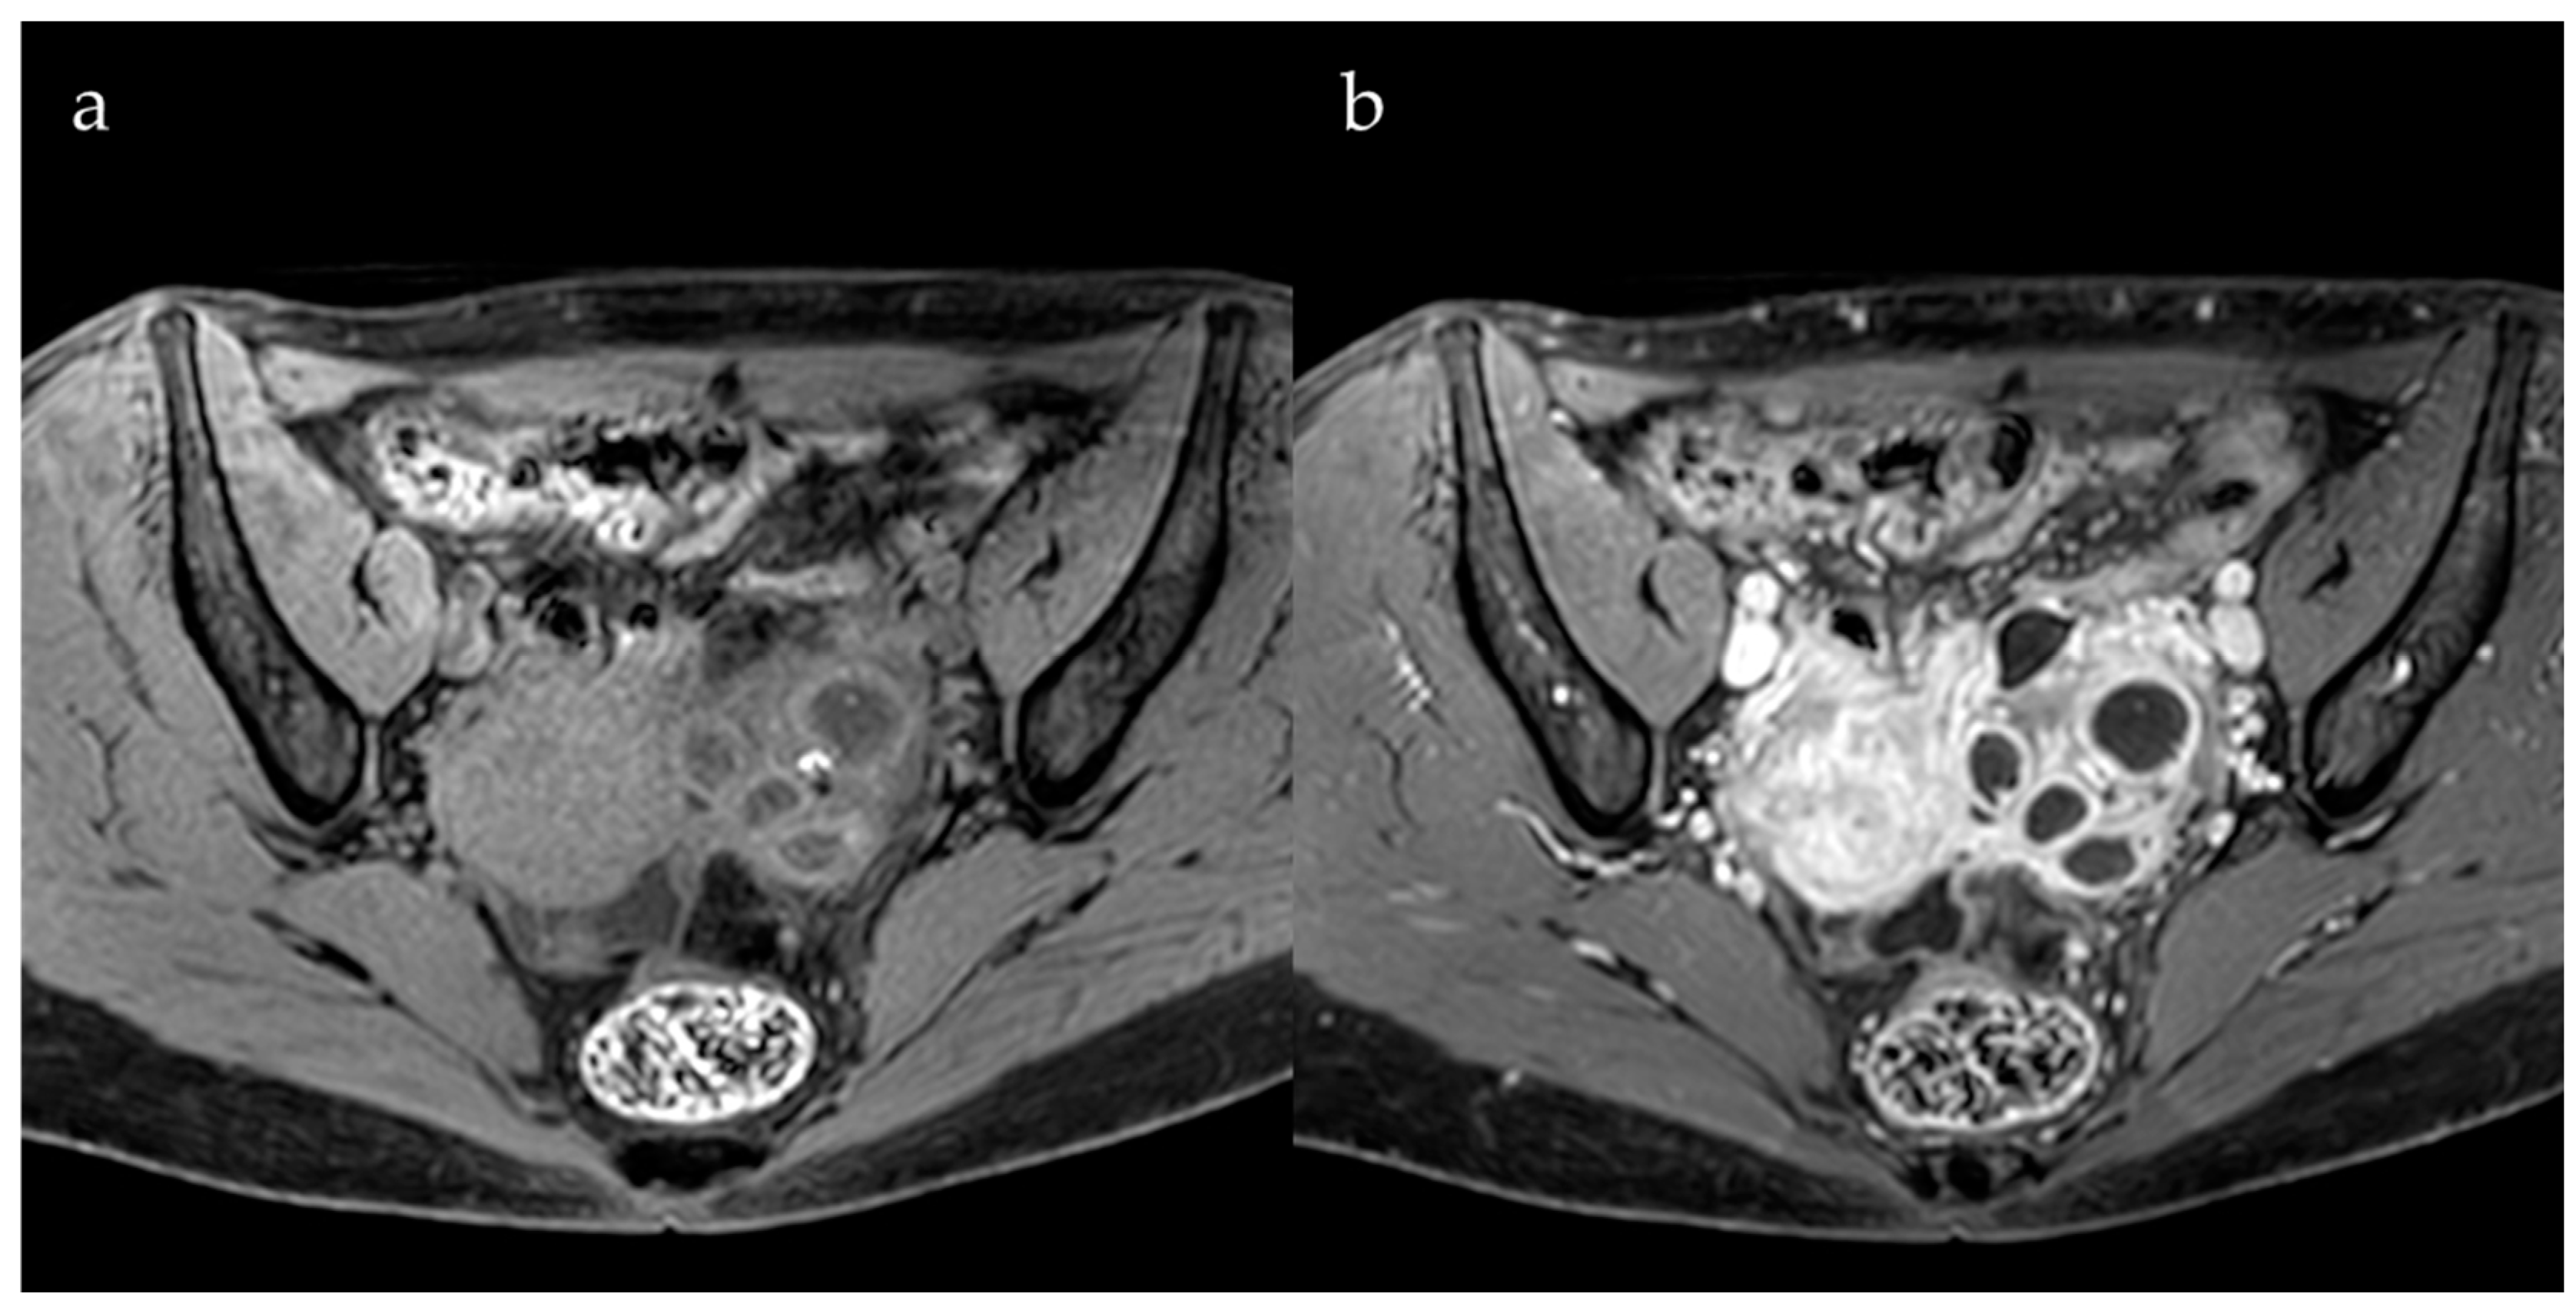

2.2. Deep Pelvic Endometriosis

3. Role of Contrast Agents